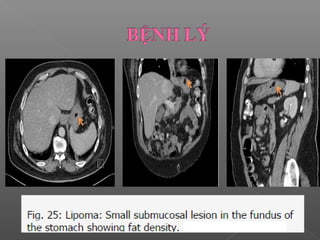

 Tổn thương khu trú lớp dưới niêm mạc

(Presentation as focal submucosal lesion):

 Dễ bỏ sót trên CT do kích thước nhỏ  cần phải

đánh giá kĩ.

 Tổn thương nằm hoàn toàn ở lớp dưới niêm mạc

 Hay gặp nhất là leiomyoma và lipomas

 Leiomiomas, lipomas, u bao dây thần kinh

U lành tính ít gặp

Lipomas: thấy thành phần mỡ của u

 Dễ bỏsót trên CT do kích thước nhỏ  cần phải đánh giá kĩ.  Tổn thương nằm hoàn toàn ở lớp dưới niêm mạc  Hay gặp nhất là leiomyoma và lipomas